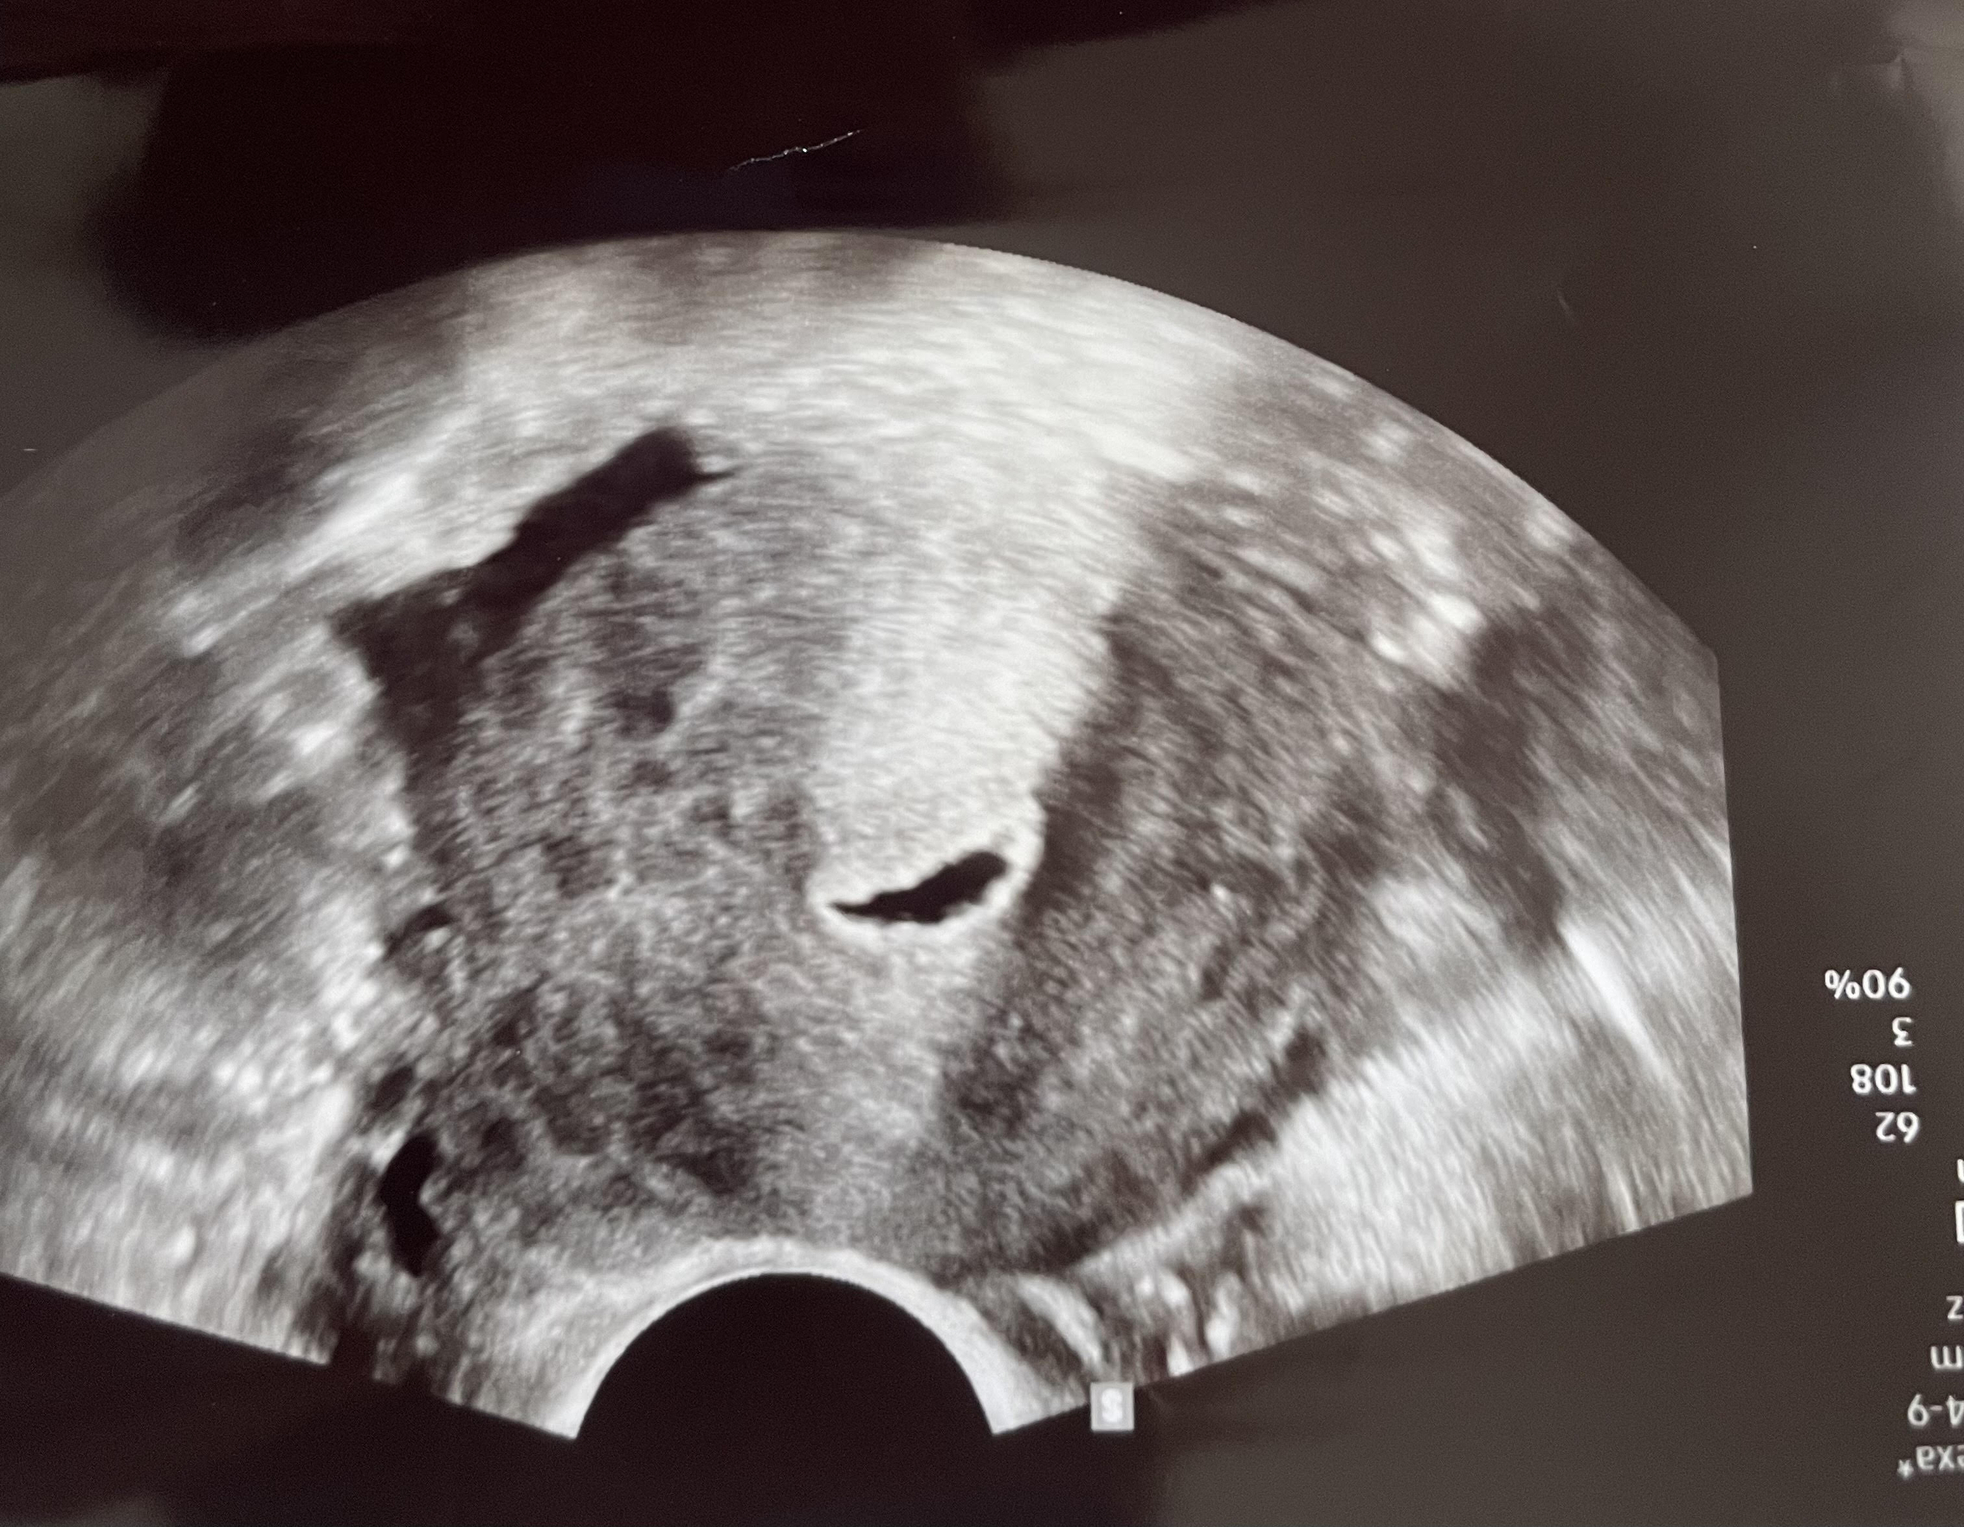

Any questions?: Ugh, so many. But here's one: I went in for an ultrasound the other day (not a day 3 baseline), and I had 14 follicles in my right ovary and six in my left (because I had a big follicle measuring at 27mm taking up space). At first I thought these numbers were good, but then I went on Google (terrible idea) and now I'm wondering if the high number could be a sign of PCOS. I really shouldn't Google things, but I don't have my follow-up with the RE until next month.